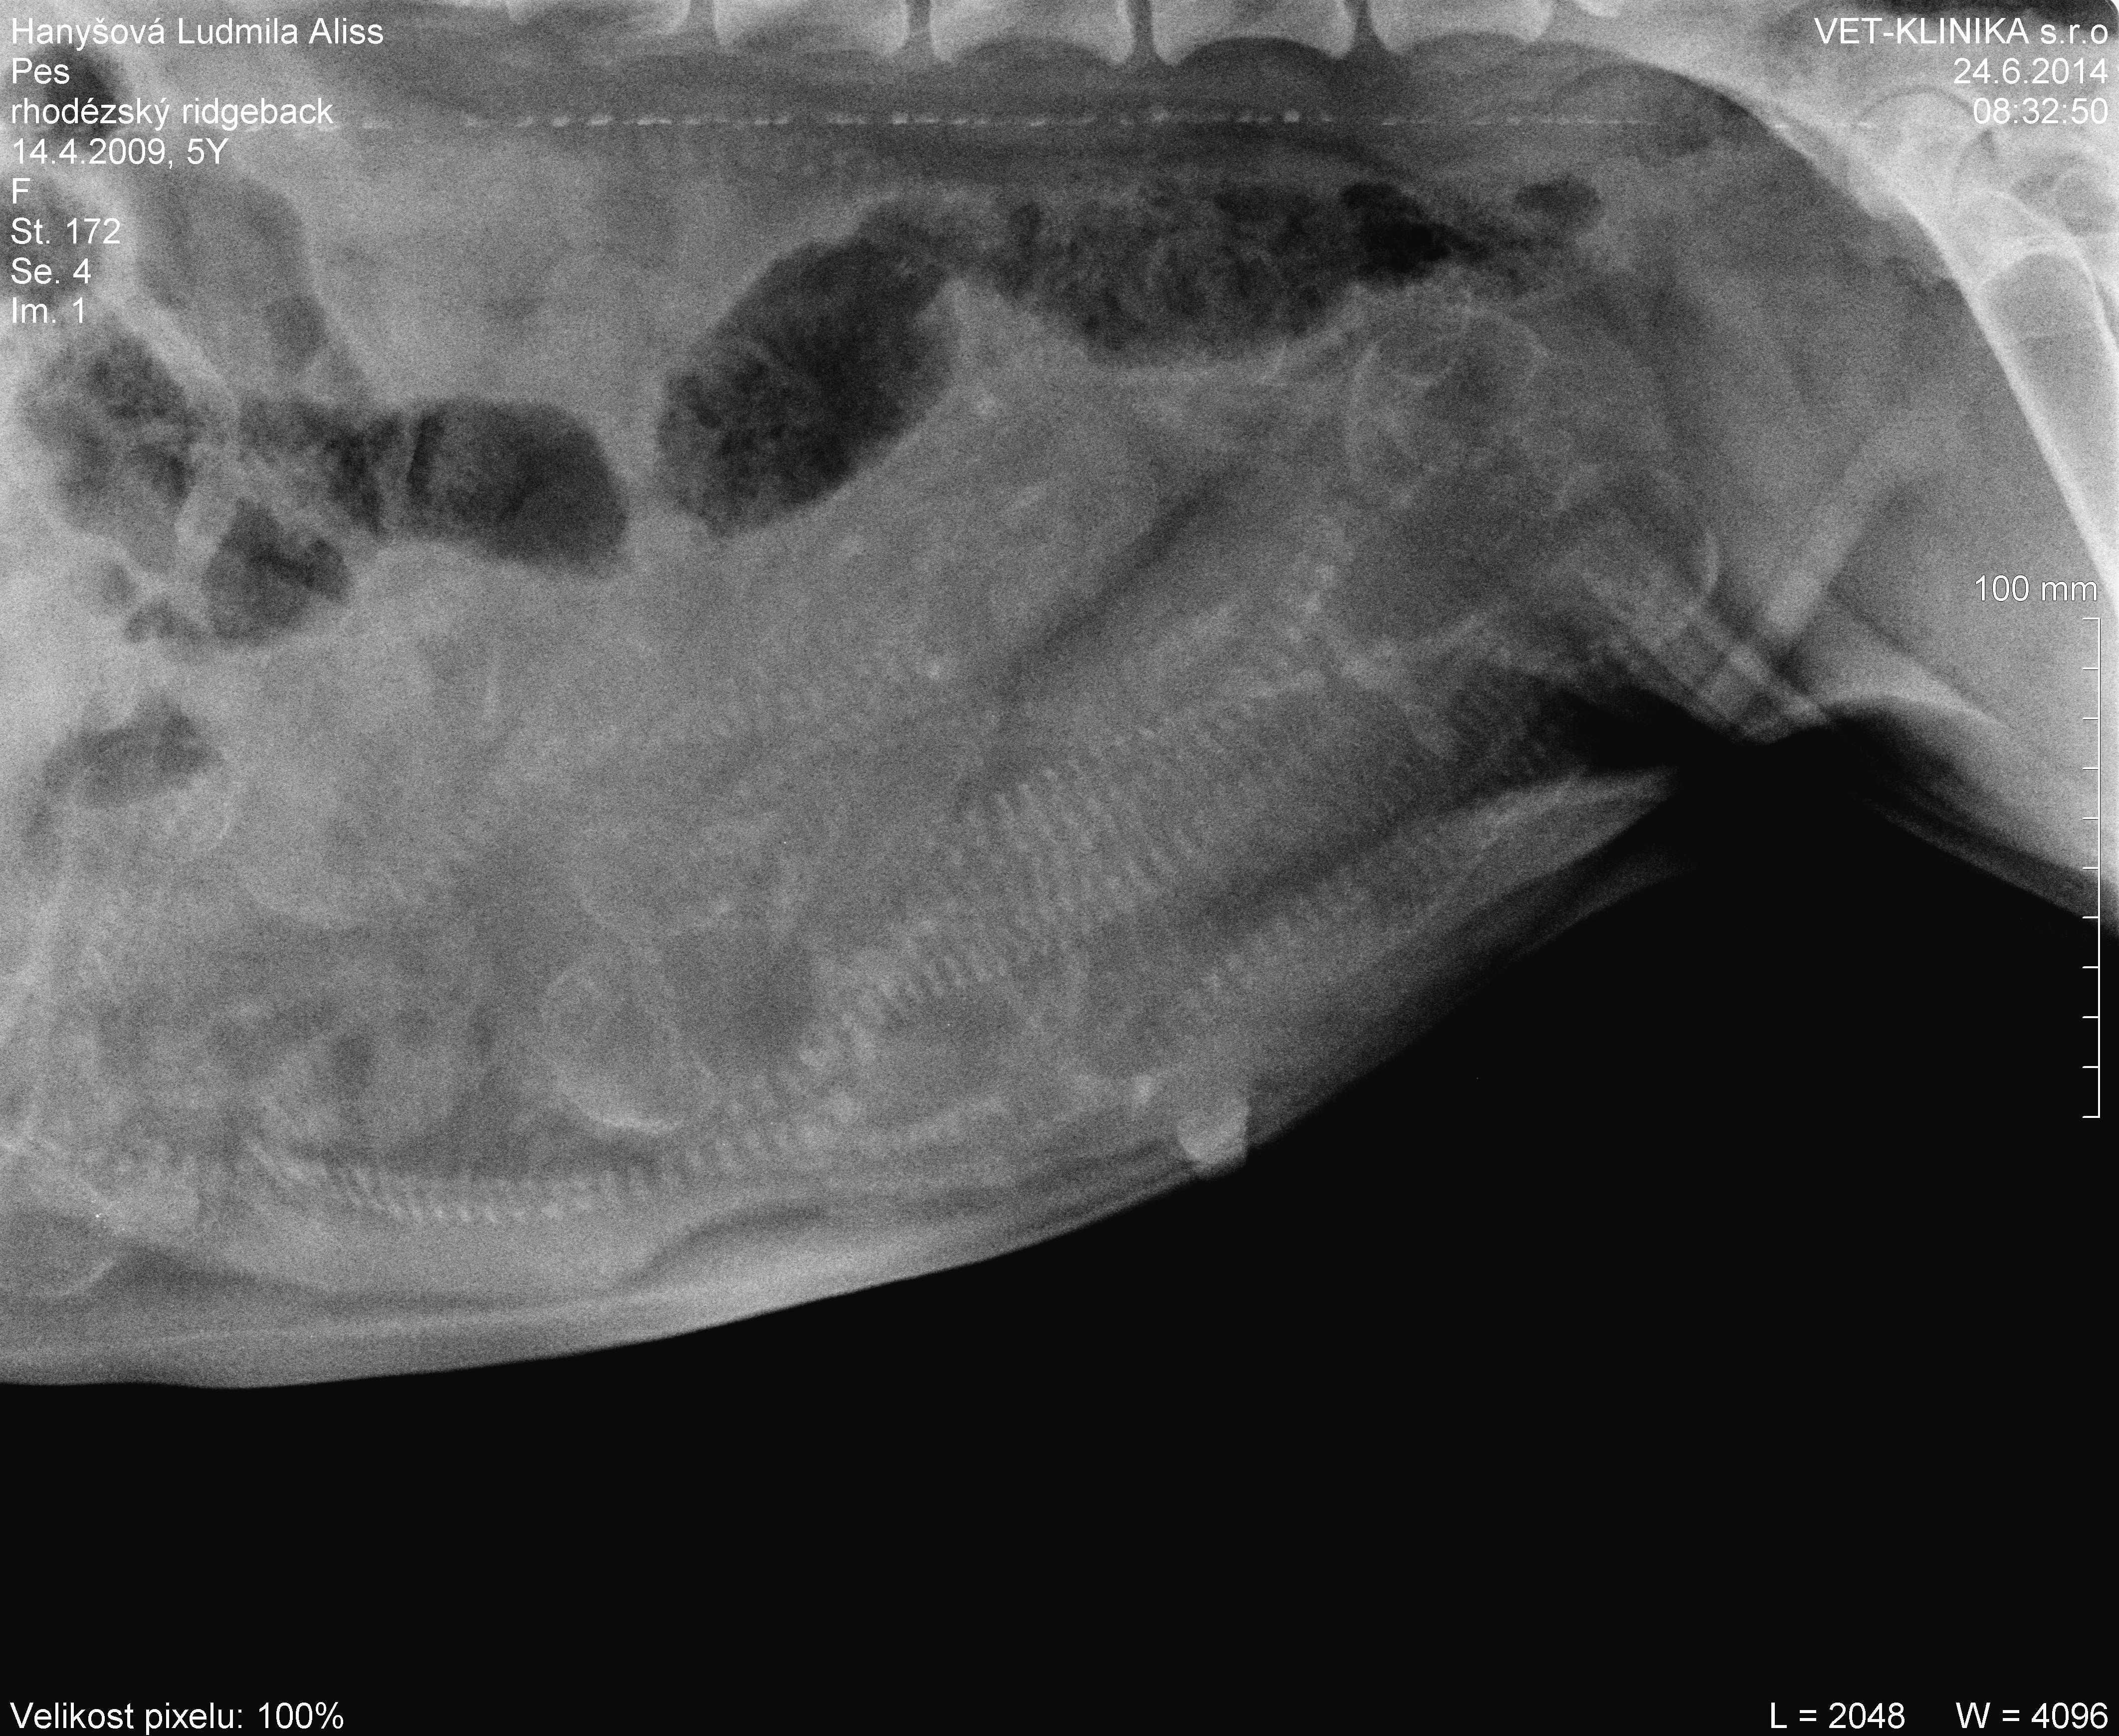

Tak jsme měli tentokrát pocit, že potřebujeme mít jistotu. Už dvakrát nám doktoři říkali, že těch miminek nebude moc...dvakrát jsme skončili s počtem 14. Tentokrát už po sonu říkala paní doktorka, že tohle vážně nebude početný vrh. Faktem je, že jsem měla z Geenky pocity, že si březost užívá, ale že by bylo bříško jóó plné mi rozhodně nepřišlo. A tak jsme se poprvé v životě vypravili nechat si udělat rtg fotečku. No, pan doktor Ekr pravil, že 14 jich rozhodně není a že nám přeje šťastný porod i počet

, ale...Když jsme rtg otevřeli v pc byl mnohem zřetelnější než v ordinaci na velké obrazovce. Myslím, že s počtem 6 - 8 se můžu rozloučit. Řekněte mi, jak to vidíte vy?